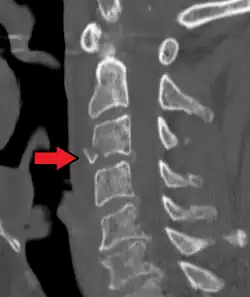

On CT scan or X-ray, a cervical fracture may be directly visualized. In addition, indirect signs of injury by the vertebral column are incongruities of the vertebral lines,[7] and/or increased thickness of the prevertebral space:[8]

-

X-ray of normal congruous vertebral lines